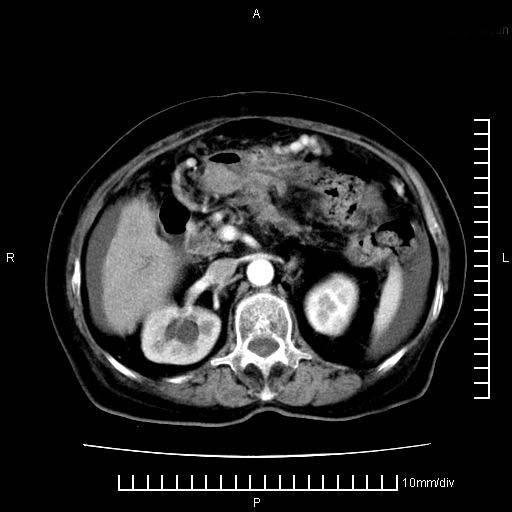

标题: CT28280:腹部增强:女性,80岁

上腹疼痛月余,外院核磁诊断胰腺癌。现临床示右下腹可明显触及包块,可片子上怎么没有看到?

1.胰腺颈体部癌。

2。腹腔积液。

胰腺体部癌累及周围器官,腹膜、粘连

胰腺体部癌累及周围器官,腹膜、粘连,临床摸到的可能是粘的组织

胰腺结构模糊,胰尾部见囊性包块,周围脂肪密度增高,左肾前筋膜增厚,胸水、腹水。不符合胰腺ca伴腹膜腔转移。考虑胰腺炎伴假性囊肿形成、胸腹腔积液。

右肾盂囊肿。

1)考虑胰腺癌并胰腺假性囊肿形成。2)肝内低密度灶,不排除转移。3)右肾盂积水。4)腹水。5)右侧胸腔积液并右肺下叶部分膨胀不全。